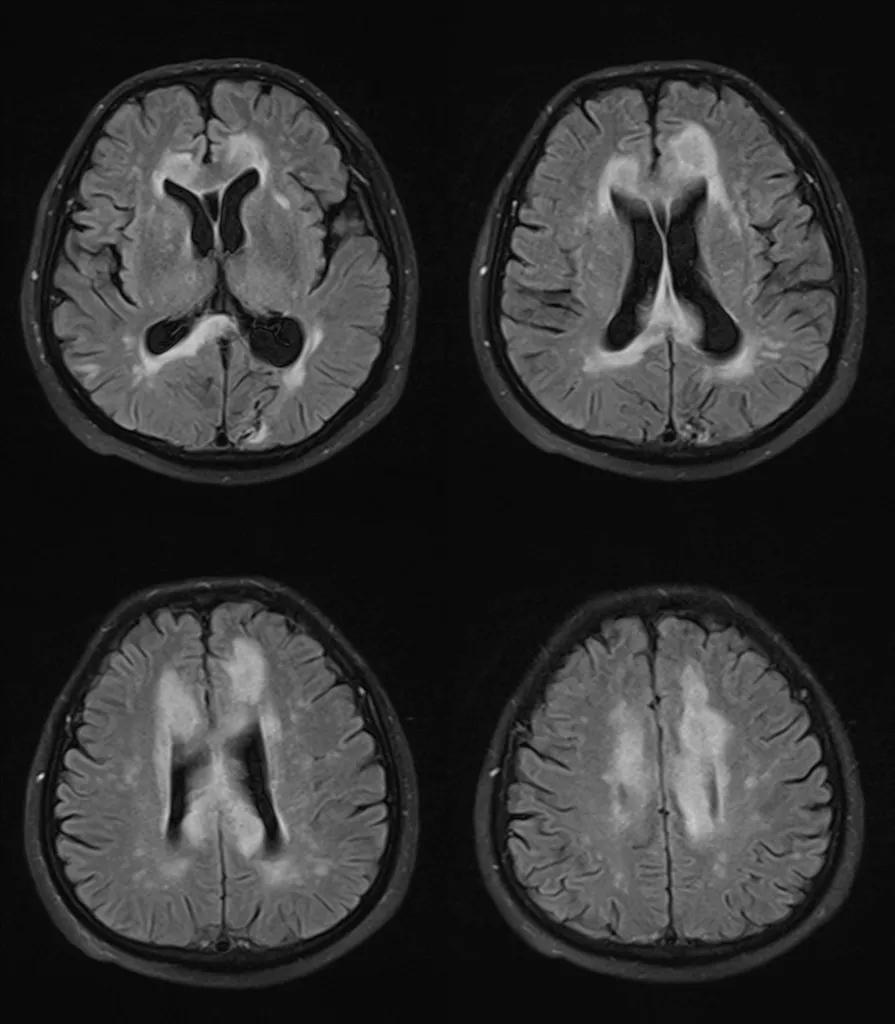

上排:原发性胼胝体变性急性期

下排:原发性胼胝体变性慢性期,表现为胼胝体萎缩、软化

急性期原发性胼胝体变性(胼胝体压部及体部病变,CT呈低密度,T1WI呈稍低信号,FLAIR呈稍高信号,扩散受限)向慢性期转变,慢性期胼胝体压部病灶出现坏死或囊变,FLAIR呈低信号